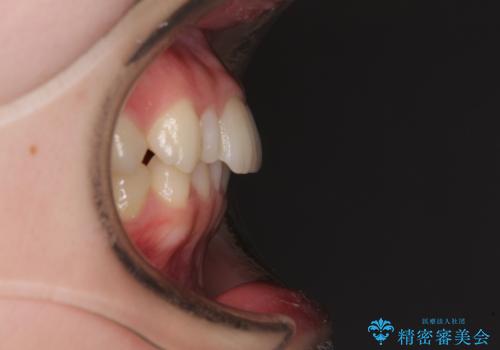

- 歯列のデコボコを気にして来院された患者様です。

安価に速やかに治療をしたいとのことで、メタルワイヤーにより矯正治療を行うこととしました。

上顎左右側切歯は矮小歯であり、矯正治療開始前にオールセラミッククラウンによる形態修正を兼ねた補綴治療を提案しましたが、特に気にならないとのことで、歯冠形態はそのままとしました。